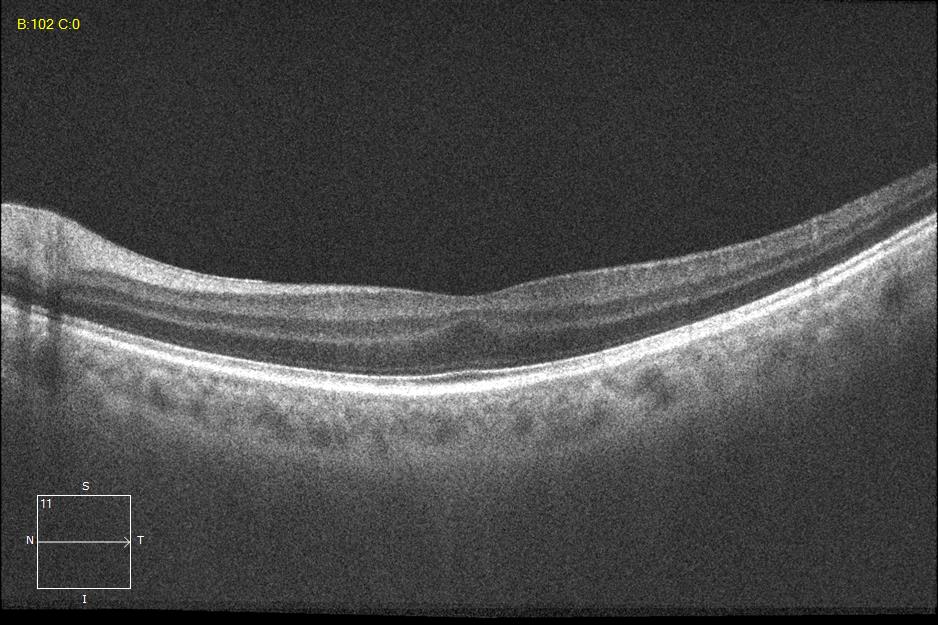

Three different patients with isolated grade 1 foveal hypoplasia. The definitions of fovea plana and foveal hypoplasia have led to controversy among experts. The term fovea plane refers to the anatomical absence of a foveal pit. An estimated 3% of children with clinically normal eyes have an underdeveloped foveal pit on OCT. According to some experts, a foveal pit is not absolutely necessary for foveal cone specialization. A diagnosis of fovea plana alone does not automatically herald functional disability. It is possible to maintain adequate visual acuity in an eye with a fovea plana. Foveal hypoplasia refers to an underdeveloped fovea with vision loss. Foveal hypoplasia has also been seen in conditions such as aniridia, albinism, achromatopsia, nanophthalmus, and incontinence. pigment and premature retinopathy.

Grade 2 foveal hypoplasia has all the features of grade 1, except that there is no pit.